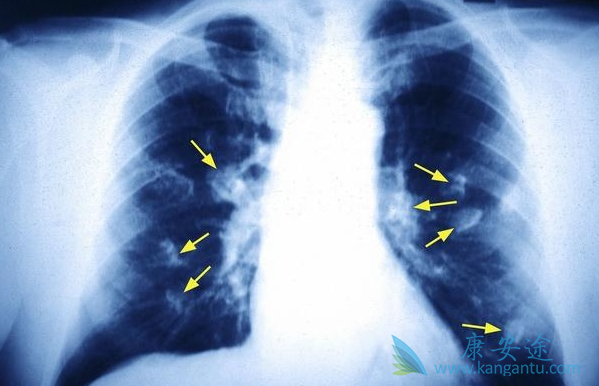

众所周知,“谈癌色变”是很多人的第一反应。专家指出,对于恶性肿瘤,越早发现,越能增加康复治疗的概率。然而,对于肺癌而言,却总是发现的很晚。因此,了解肺癌晚期的症状就显得尤为重要,发现不及时也成为很多肺癌患者迁延难治的根本原因。那肺晚期的症状有哪些?

声音嘶哑是肺癌晚期患者最常见症状。控制左侧发音功能的喉返神经由颈部下行至胸部,绕过心脏的大血管返行向上至喉,从而支配发音器官的左侧。因此,若肿瘤侵及纵隔左侧,使喉返神经受到压迫,声嘶便产生了,但却无咽痛及上呼吸道感染的其它症状。有发生区域性扩散的肺癌晚期患者几乎都有不同程度的气促。

肺癌患者出现无原因的头疼、呕吐、视觉障碍以及性格、脾气改变可能为肺癌转移到脑部引起的颅内高压或脑神经受损所致。常见于小细胞肺癌、腺癌类型。肺癌除上述几种常见转移部位外,较少见的转移部位有皮肤、皮下组织、肌肉、腹腔内、心脏等部位的转移,症状常与转移部位相关。如转移到心脏可出现胸闷、心悸甚至气急、晕厥、心律紊乱等症状。